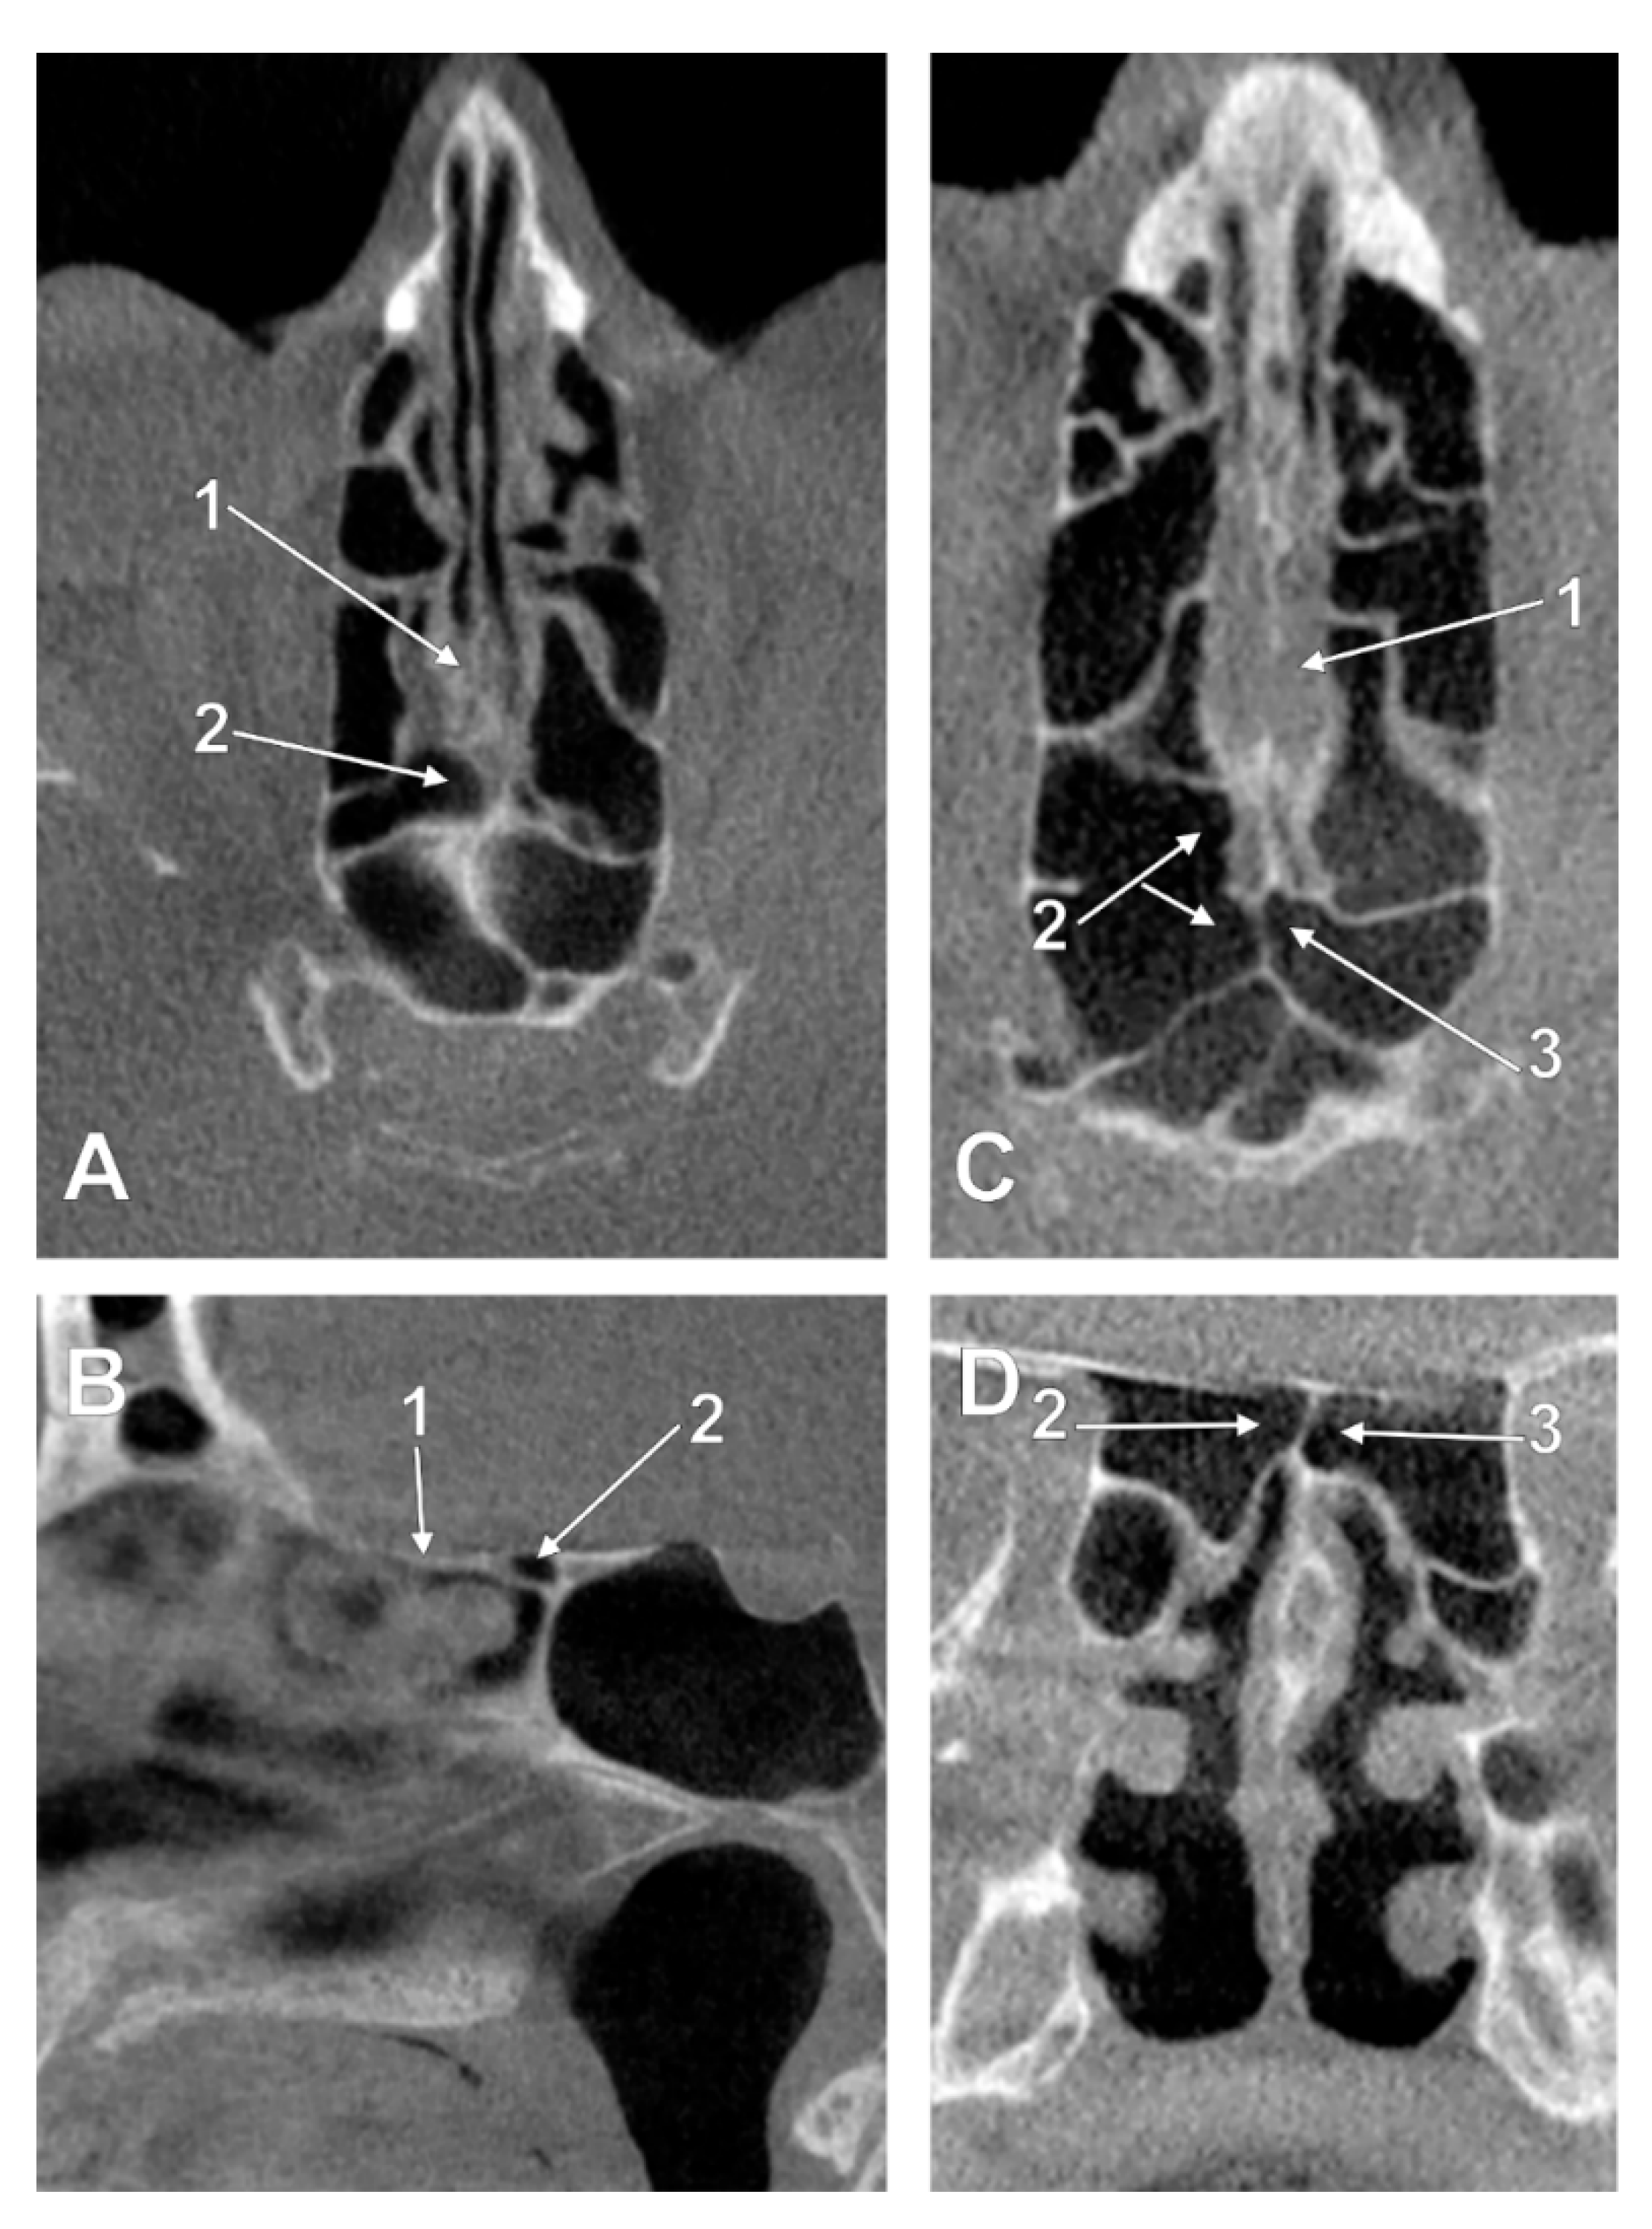

3.2. Sphenoidal Origin of Nasal Roof Pneumatization